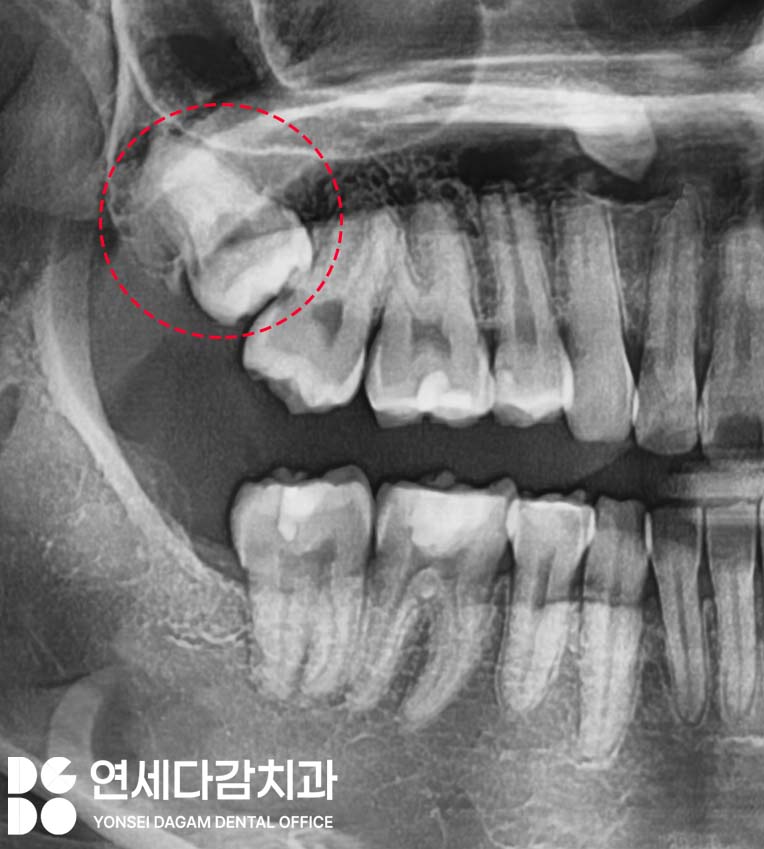

무엇보다 위턱 큰 어금니의

뿌리 부위는 상악동 저와

근접해 있기 때문에

주의하지 않으면 천공이 일어나기

쉬운 부위입니다.

개롱역 치과 에서는 이럴 땐

더 세심한 작업을 목표로 하게 됩니다.

따라서 CT를 필수로 촬영하여

3차원적인 구조를

분석하는 것이 중요합니다.

이를 빼기 전 이렇게

사전 정보를 수집해서

주변 구조를 파악하여

발치 계획을 수립하는 것이 중요합니다.

CT 영상을 통해 사랑니와 상악동의

정확한 위치 관계,

주변 조직과의 관계를 파악할 수 있어

안전한 발치를 위해서는 필수 검사입니다.